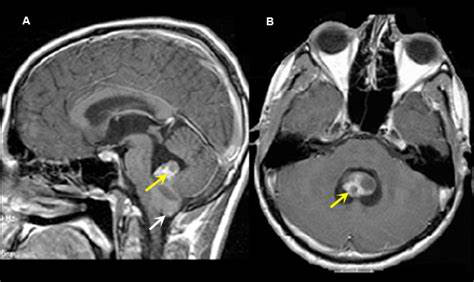

胶质瘤二级 术后生存期,根据组织学和临床标准,胶质瘤被分类为I级至IV级。 I级肿瘤通常是低度恶性的,并且可以通过完整的手术切除来治疗,主要发生在儿童中,并被认为与II-IV级...